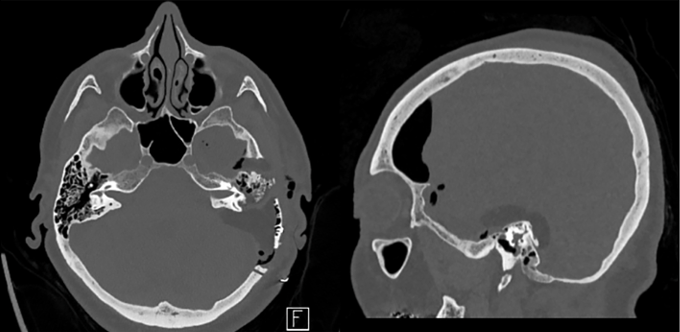

福教授的决策策略是:放弃内镜经鼻入路的选择,转而选择经后岩骨入路的手术方案。这一入路最初由Hakuba等人于1985年提出,主要用于颅咽管瘤的手术治疗过程。由于垂体细胞瘤与垂体漏斗部区域的颅咽管瘤在解剖位置上存在高度相似性特点,这一入路可以提供从后方到前方、从下方到上方、从外侧到内侧的多维度手术视野,能够直接观察肿瘤与周围关键结构的解剖关系状态,有助于从垂体柄的后方区域进入,最大程度地保留垂体功能的完整性,同时增强对穿孔血管的可视化控制程度。此外,该入路引发脑脊液漏并发症风险的概率也相对有限些。

这套精密的治疗策略为手术提供了坚实的支撑基础。福教授沿着肿瘤组织的边界区域,在垂体柄结构和视交叉组织旁边保留薄层残余后,将肿瘤的主体部分安全完整地进行了切除操作。整个手术过程中,没有发生一次意外的出血状况,没有一根重要神经结构受到明显的损伤影响。

安娜的术后恢复状况令人感到振奋:手术之后没有出现新发的神经功能障碍表现,没有发生内分泌功能的损伤现象,一周之后顺利出院回家进行后续的康复调养。组织病理学检查结果最终证实了垂体细胞瘤的临床诊断结论。

术后六个月进行随访检查时,影像结果显示残余的肿瘤组织没有任何的生长迹象表现。安娜的视力状况逐渐恢复良好状态,又能清晰地看见这个多彩的世界了。